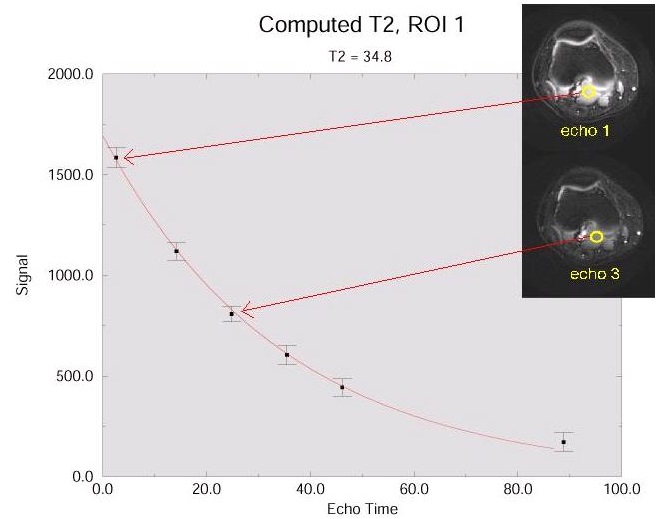

T2 MAP is used to noninvasively detect changes in the collagen component of the extracellular matrix of cartilage. T2 MAP acquires multiple scans at each location; each set of scans has a unique TE resulting in a set of gray scale images that represent different T2 weighting.

The acquired data can be processed in READY View to produce T2 color maps, which demonstrate more subtle changes in cartilage ultrastructure that are not visible on gray scale MR images. The T2 map and the parametric images produce visible image contrast changes in early stages of cartilage degeneration such as osteoarthritis.

The number of TEs per scan (not selectable) determines the number of images that are acquired at each location. For example, if 10 locations are prescribed and 6 (number of TEs) per scan are prescribed, then there are 10 data sets with 6 images per location. Each image within a data set or location has six unique T2-weighted images because all lines of k-space are filled with one (each individual) TE. This differs substantially from the traditional Fast Spin Echo sequence.

The collagen in the radial zone of articular cartilage, close to the subchondral bone is highly ordered, with only small quantities of mobile water. By contrast, the collagen in the transitional zone is more randomly oriented, with increased mobile water and more prolonged T2 values. Increased T2 relaxation times within cartilage have been associated with matrix damage, particularly loss of the orientation of the collagen matrix.

Disruption of collagen --> increased mobility of water -->prolongation of T2 relaxation times.